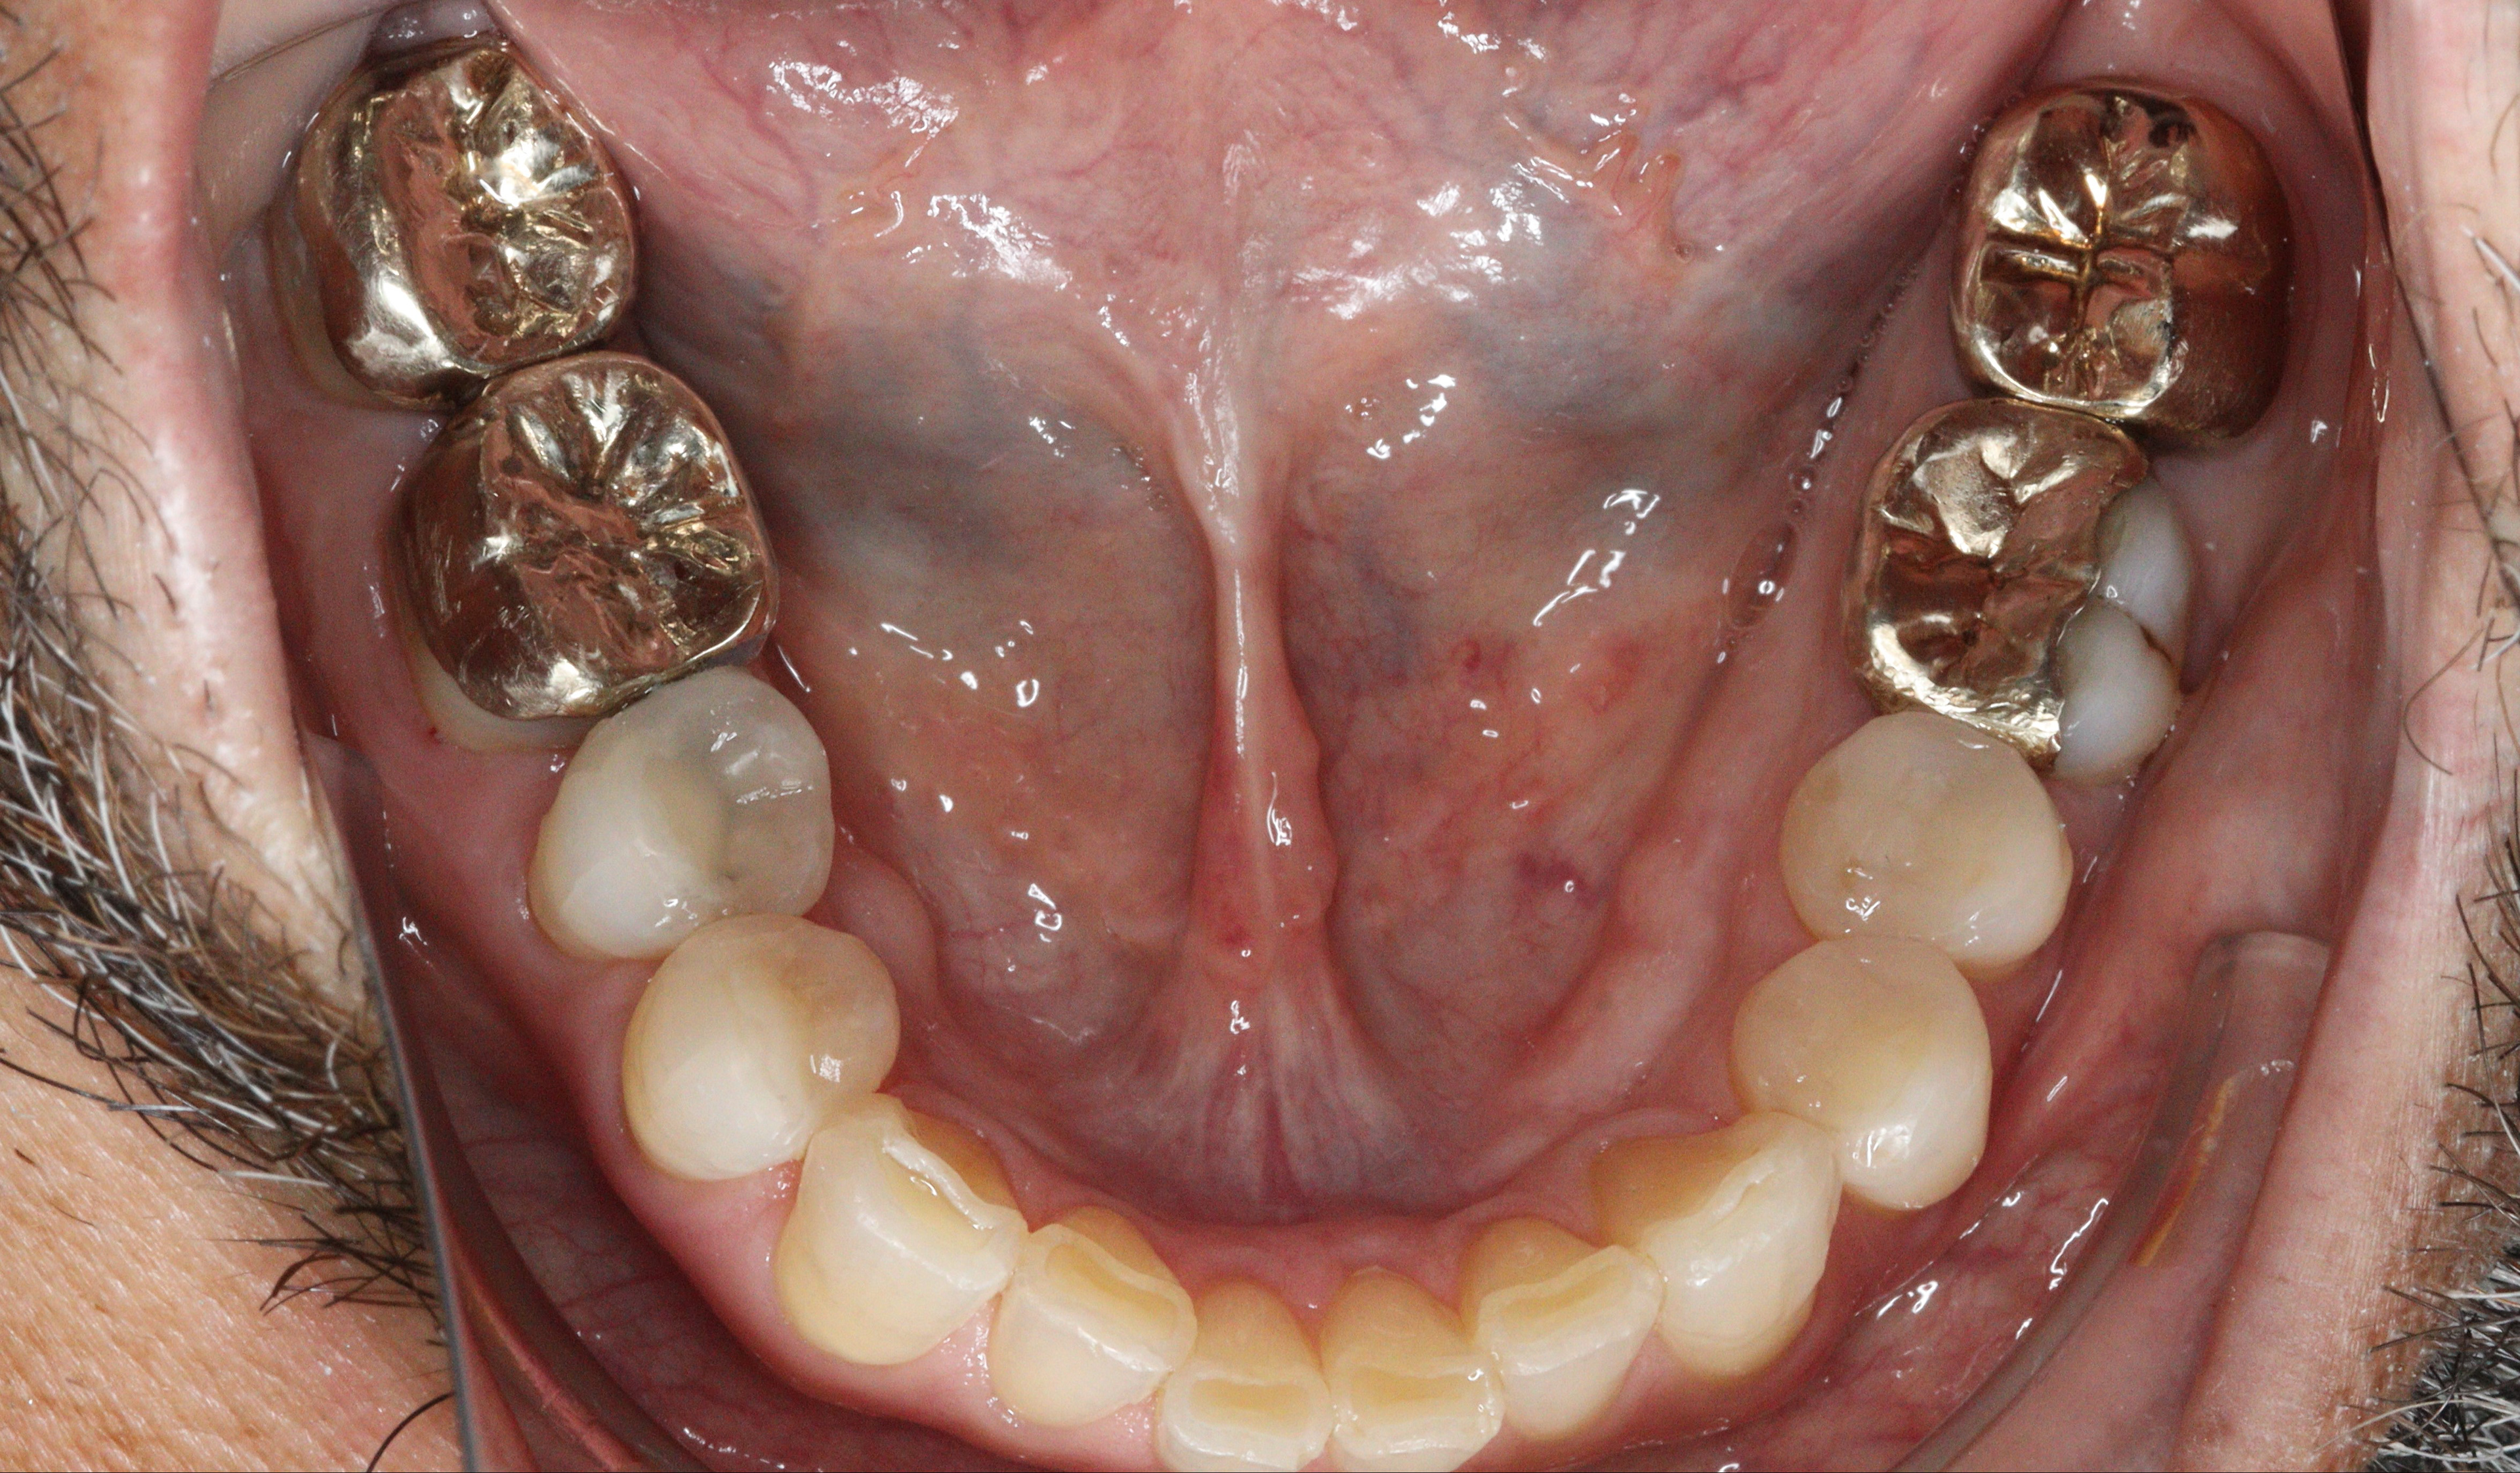

A golden heart, A golden smile.

Increased OVD and regained anterior guidance. Combined composite, gold and ceramic. Stay tuned for 13.